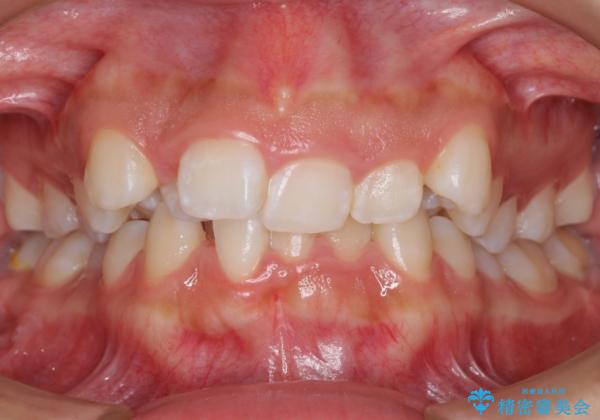

前歯のがたがた 前歯が内側に傾いている

- 前歯のがたがたを主訴に来院。

上の歯並びが前にずれて、さらに前歯が内側に倒れて過蓋咬合を呈していました。

奥歯のかみ合わせもずれていたため、上の奥歯を後ろに下げる処置をミニスクリューを用いて行いました。